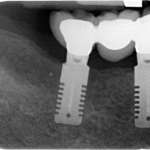

L’evoluzione dell’implantologia ceramica – Indicazioni all’utilizzo degli impianti ceramici bi-componente

L’evoluzione del settore implantologico si è indirizzata negli ultimi anni verso la ricerca di materiali alternativi al titanio. Gli impianti in zirconia, inizialmente impiegati nella loro variante one-piece, hanno avuto un ulteriore sviluppo grazie all’introduzione della versione two-piece. Questo aggiornamento monografico ha come obiettivo quello di descrivere le peculiarità degli impianti in zirconia two-piece, prendendo in esame la letteratura scientifica al fine di comprendere a oggi il tasso di successo di questi impianti, le caratteristiche morfologiche, i vantaggi e gli svantaggi che ne conseguono oltre che le indicazioni cliniche quali, per esempio, le riabilitazioni full-arch.